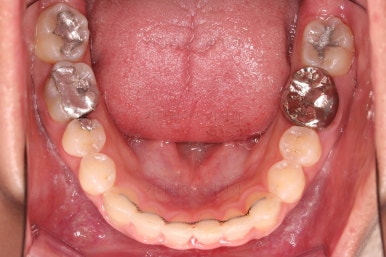

악궁확장 이후에 교정장치를 부착하고 치열을 가지런하게 해줘요.

이번에 사용한 장치는 엠파워 메탈이라고 하는 자가결찰 메탈 장치입니다.

거듭 말씀드렸지만 메탈이라고 다 옛날의 구식 장치가 아니에요.

"자가결찰" 인지 아닌지 여분가 훨씬 중요한데요.

"자가결찰" 메탈장치라면 치료효과가 좋은 "자가결찰"장치의 한 종류이므로 기능이 매우 좋은 장치랍니다.